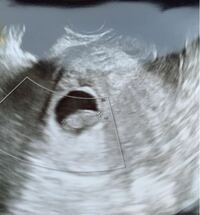

36歳です。 パニック障害でメイラックスとデパス服用してました。 5週で胎のう確認できず、6週3日でやっと15mmの胎のうのみ確認できました。今日8週1日で受診しましたが胎芽も心拍も確認できず、25mmの胎のうと卵黄のうだけでした。 先生は胎のうの形も崩れてないし赤ちゃんの栄養袋が見えて 妊娠8週目の3度目の診察の時に、 前回見えていた 心拍が確認できないと先生に 地獄の宣告をされました。 胎児はちゃんと成長していて 2頭身になっていたのに、 心拍だけが 確認できなかったのです。 先生曰く、 胎児は前回よりも成長しているので、 妊娠8w 心拍が確認できない 妊娠8w、2度目の妊婦検診 また土曜日に主人とクリニックを受診し 今度は主人も一緒に内診室に入り 赤ちゃんの心拍が見えるのを楽しみにしていました。 ところが、エコーには 赤ちゃんかな・・・?

(結論)妊娠7週で心拍確認できない=100%流産ではない。ただし、条件あり この調査に限って言えば、 妊娠7週中に心拍が確認できなくても自然妊娠なら過度に心配する必要はないが、体外受精の場合は100%妊娠継続の可能性はないと思った方が良い 、という結論に至りました。 妊娠8週で2回目の健診に行きました。 1回目は5週半くらいと言われ、胎嚢(たいのう)がmmで胎芽(たいが)は確認できませんでした。 2回目の健診で、胎嚢が26mm、胎芽は28mmで心拍は確認できないとのことでした。 次は2週間後に健診に行きます。 心拍が確認できません カテゴリー: 妊娠中の体の変化 > 妊娠2ヵ月(4~7週) |回答期限:終了 |そらちゃんさん 回答数 (24) シェアする ツイートする LINEで送る 妊娠初期、まだ心拍確認できません ・生理周期は28日~38日などバラバラ